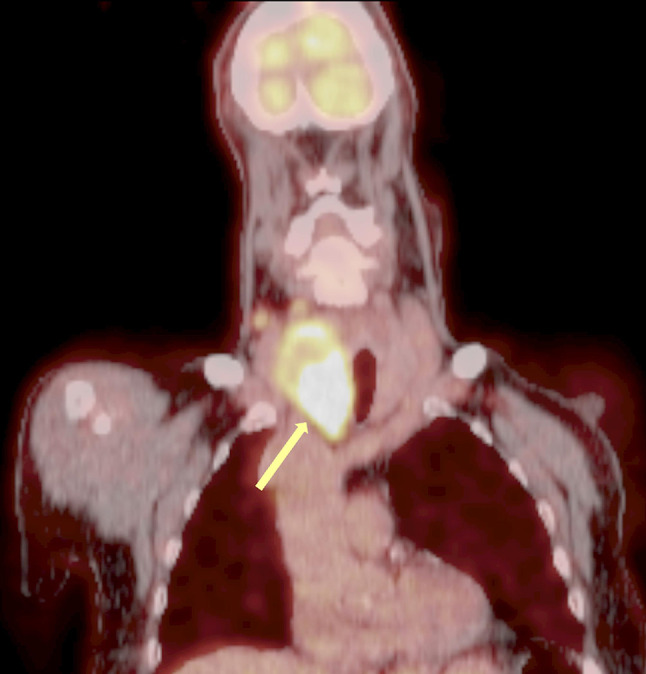

Background: Thyroid angiosarcoma is a rare, highly aggressive malignancy of endothelial origin, characterized by rapid growth, invasive behavior, and a high metastatic potential. While most cases are reported from the Alpine regions of Europe, its occurrence elsewhere is exceedingly rare. The aim of our review is to report a case of thyroid angiosarcoma and provide a systematic review of the literature, focusing on clinical presentation, diagnostic strategies, and treatment outcomes.

Results: A systematic review of 72 cases of thyroid angiosarcoma reported in 52 articles was conducted. The median patient age was 66 years, with female predominance (4:3). Most patients presented with a rapidly enlarging thyroid mass and compressive symptoms. Diagnosis required a combination of histopathology and radiologic imaging, with Fine Needle Aspiration Cytology as the initial tool in 47% of patients. Total thyroidectomy was performed in 67% of cases, and 42% of patients received adjuvant therapies. The prognosis remains poor, with a median overall survival of 28 months and a 3-year survival rate of 40%.